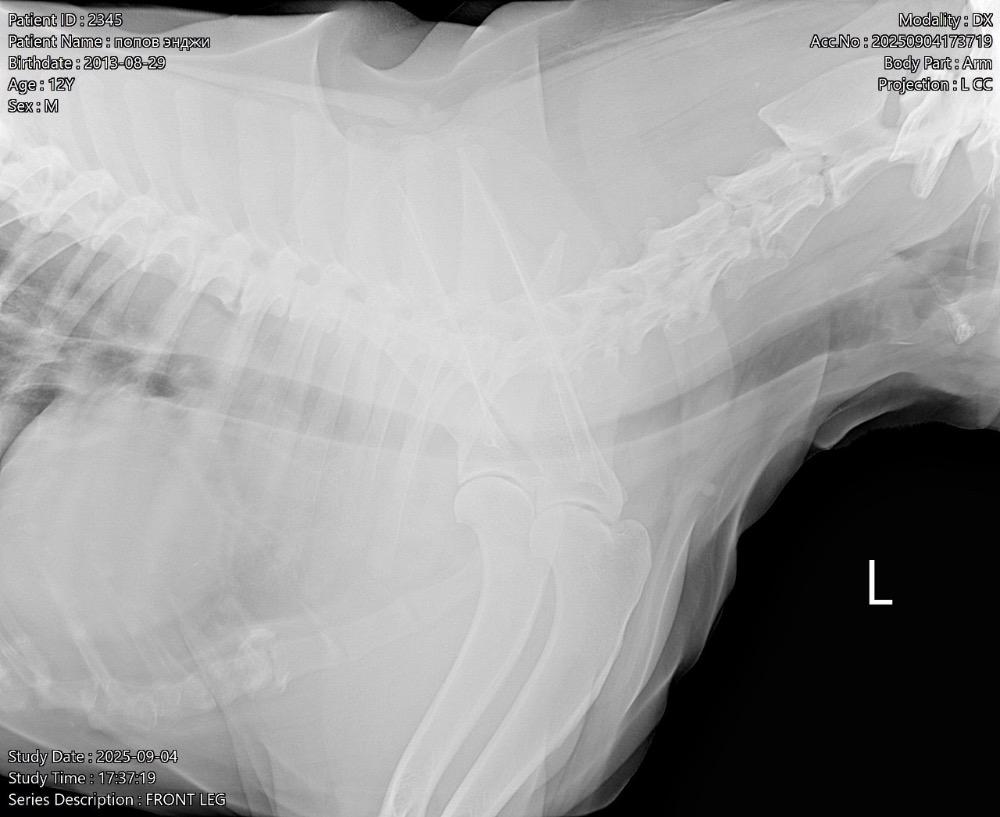

Татьяна13 Опубликовано 24 ноября, 2025 Опубликовано 24 ноября, 2025 (изменено) Всем здравствуйте! В июне началась проблема с лапами. Поставили диагноз-остеоартрит! Робексера+пк мерц прекрасно справлялись! На прошлой неделе собаке резко стало худо. Она начала часами без остановки дышать, иногда пристанывая. Было ясно, собаку что-то беспокоит…. В ветеринарке сдали анализ крови, сделали узи брюшной полости-ничего критичного… Врач решил, что Робексера уже не помогает, заменили на Фироко 227 мг + также оставили пк мерц. Добавили усросан, чтоб чуть полечить печень, так как небольшие отклонения есть… За 3 дня улучшений не вижу. Собака все также дышит без остановки часами, иногда пристанывая, второй день отказывается от корма (но вкусняшки ест), воду из миски пить отказывается (но пьет в ванной из душа и ест снег). Сегодня как будто начали отказывать задние лапы-она волочит ими. Вновь погнали в ветеринарку, они настаивают, что Фироко препарат хороший, сильнее его уже нет. Ждите! Чего ждать? Обезболивающее должно действовать же сразу…. Сказали, что тут скорее всего произошло защемление позвонка! Поэтому задние лапы не слушаются! И либо опять же ждите, либо делайте мрт, а потом операцию (собаке без пяти минут 12 лет, кстати!). Вдобавок выписали: Габапентин. В четверг хотят еще прокапать Хиовет. Сейчас, солнце мое спит, ходить не может. Когда просыпается, пытается встать и начинает дико плакать! И снова ложится! Люди, чем помочь собаке моей? Столько таблеток выписали… Как не навредить😭 У меня уже сердце болит… Изменено 24 ноября, 2025 пользователем Татьяна13 1